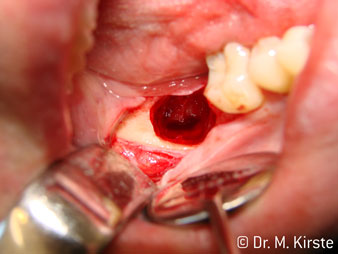

Угол 45° наконечника был выбран специально с учетом широкого круга преимуществ. Коллеги, которые работают в хирургии, и для которых этот наконечник был изначально создан, быстро оценят возможность эффективно работать в очень стесненном пространстве. В частности, при удалении зуба мудрости (рис. 2) не нужно сильно раздвигать мягкие ткани в области щеки (рис. 3). Конструкция головки наконечника в сочетании с небольшим поворотом головки во время препарирования позволяет быстро и безопасно выполнять работу в области задних коренных зубов.

Профессиональная конструкция подшипников внутри головки обеспечивает тихую работу бора; впечатляет атравматичное разделение зуба и корня (рис. 4-9).

Fig. 2

Fig. 3